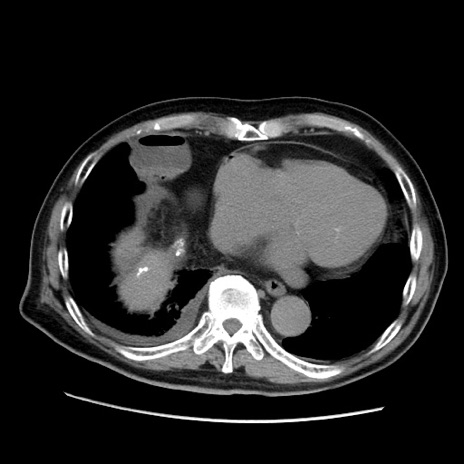

冠状断像

【症例】70歳代男性

【現病歴】肝硬変・肝細胞癌にてかかりつけの方。約9時間前に食後より腹痛出現。症状が徐々に増悪し、嘔吐出現したため来院。

【既往歴】肝硬変、肝細胞癌(RFA、TACE後)